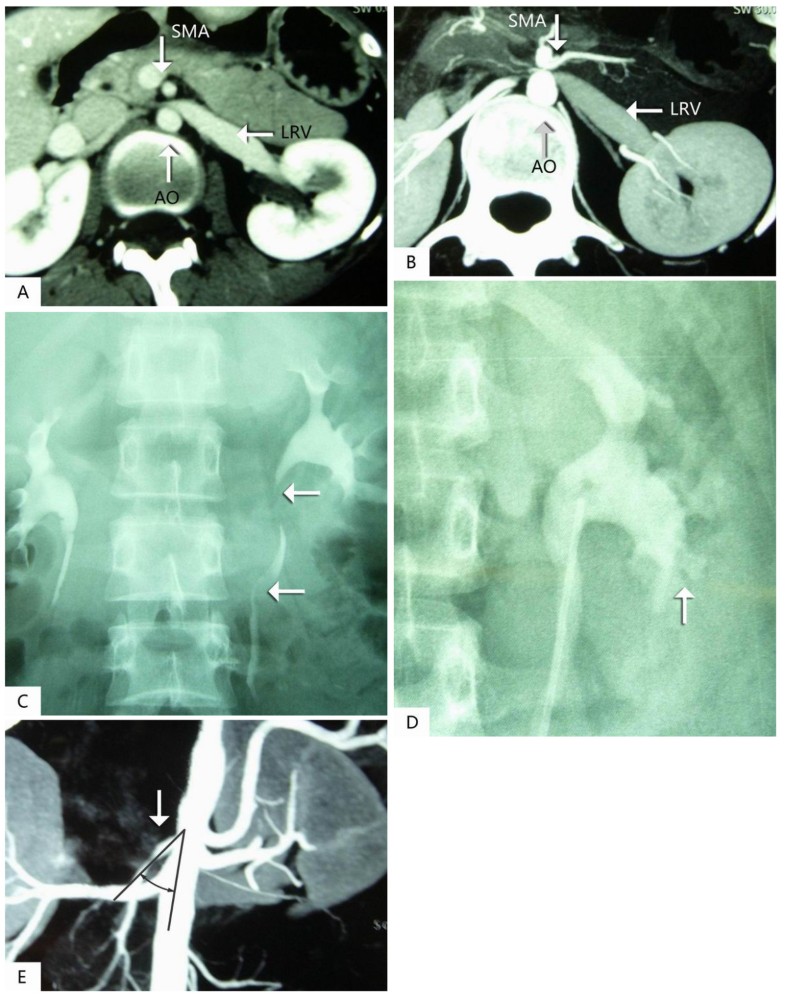

(PDF) Endovascular treatment of nutcracker syndrome Nutcracker Syndrome Autotransplantation left renal vein (lrv) transposition is often the preferred treatment for nutcracker syndrome (ncs). to report our experience with renal autotransplantation in treatment of gross hematuria caused by nutcracker. nutcracker syndrome (ncs) is characterized by entrapment of the left renal vein, leading hematuria, flank pain, and. If you have kidney stones, the stones also travel through these. Nutcracker Syndrome Autotransplantation.